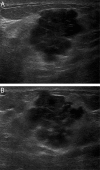

Lymphoepithelioma-like carcinoma of the breast is a rare malignancy, with fewer than 20 cases documented in the literature. Given the paucity of reported cases, there is limited information available to guide the diagnosis and management of patients with this tumor. We present a case of a 39-year-old woman with a palpable right breast mass that was initially diagnosed by core needle biopsy as infiltrating carcinoma with prominent lymphoplasmacytic stroma. Subsequent neoadjuvant chemotherapy with docetaxel, doxorubicin, and cyclophosphamide resulted in a marked decrease in the size of the mass. After wide local surgical excision, pathology revealed a lymphoepithelioma-like carcinoma of the breast. Given the excellent treatment response, our experience may help clinicians determine future therapeutic strategies for this rare breast tumor.